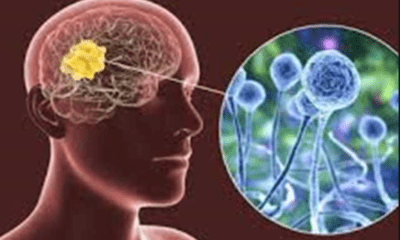

In recent days, news of the “black fungus” has been viral through social media in Saudi Arabia, Egypt, and other Arab countries. Rumors about the black...